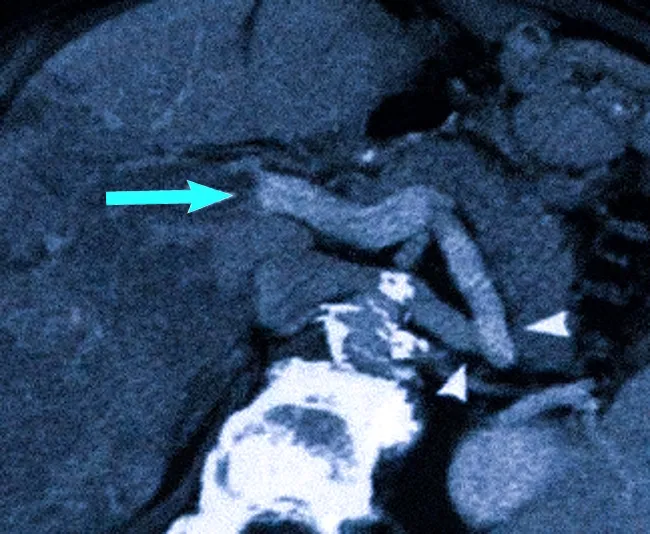

Расширенная брыжеечная вена и селезеночно-почечный шунт – путь вокруг основного кровотока (указатели), окклюзия воротной вены из-за компрессии печеночным раком (стрелка)

Ряд заболеваний печени и расстройства в системе нижней полой, портальной и печеночных вен могут вызывать портальную гипертензию, приводя к внутрикорпорационному повышению давления. В норме этот показатель составляет 5-10 мм рт. ст. Компьютерная томография позволяет зафиксировать расширение воротной вены и выявить потенциальные осложнения, такие как варикозная деформация вен, компенсирующее увеличение печени и селезенки.